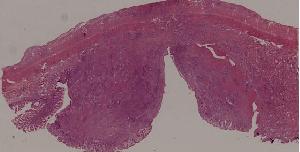

88. Chronic cavitary tuberculosis of the lung

89. Tuberculous lymphadenitis

90. Lepromatous leprosy of the skin

91. Tuberculoid leprosy

92. Typhoid fever of intestine

95. Poliomyelitis

96. Pulmonary aspergillosis

97. Amebic colitis

98. Schistosomiasis of the colon

99. Experimental acute schistosomiasis of the liver (rabbit)